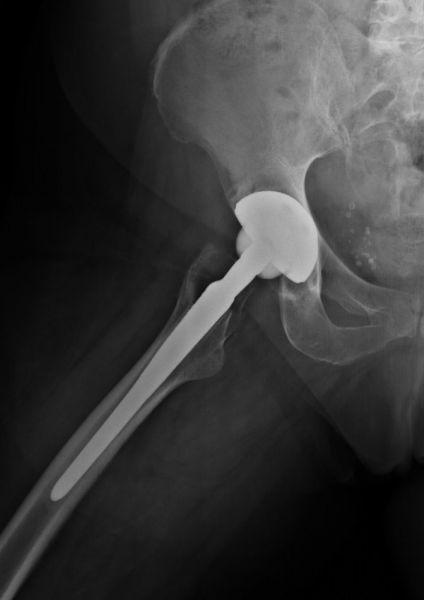

3. Periprosthetic fracture of the left femur in a 78-year- old female with a total hip arthroplasty.

Treatment: Revision of THA

I. Anteroposterior x-ray pelvis-hips shows the periprosthetic fracture. The patient referred to Mr. Papasotiriou Antonios one year after the periprosthetic fracture because of pain. The reason of pain was the loosening of the stem. II. Four months post-surgery anteroposterior x-ray left hip shows the revision of the femur stem with a new longer specific stem